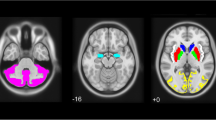

In PD, brain changes extend beyond the nigrostriatal dopaminergic pathway and consequently involve several neuronal networks, causing various non-motor symptoms5. Functional changes in these networks can be examined using 18F-Fluorodeoxyglucose PET (18F-FDG PET). 18F-FDG PET studies have identified a PD-related pattern (PDRP) characterized by relatively increased glucose metabolism in the pallidum, thalamus, pons and cerebellum, and relative hypometabolism of the premotor cortex, supplementary motor area, and parietal association regions6. PDRP expression can be quantified and has been observed to increase with disease progression and decrease with symptomatic treatment7,8. Only modest correlations exist between PDRP expression and striatal binding ratios measured by 18F-FDOPA PET or DAT SPECT imaging, indicating that the PDRP reflects more widespread functional brain changes9,10,11. In contrast to dopaminergic changes, PDRP expression shows no asymmetry, even in PD patients with strictly unilateral symptoms12.

All scans were spatially normalized to an 18F-FDG PET template in the Montreal Neurological Institute (MNI) brain space49 using the SPM12 software (Wellcome Centre for Human Neuroimaging, London, UK) implemented in MATLAB (version R2019a; MathWorks, Natick, MA, USA). The iRBD and HCNL acquired at the UMCG were already intrinsically smoothed. We applied the same amount of smoothing to 18F-FDG PET scans of PD and HC acquired in Genoa. For the PDRP-related analysis, the smoothed PET images in MNI space underwent intensity normalization using the Scaled Subprofile Model (SSM)8,50: masking, log-transformation, subject-demeaning, and grand mean profile-demeaning, based on the space defining reference group used in51. To match the symmetric PDRP, the mask we applied consisted of all nonzero voxels in the symmetric PDPR. For the ROI analysis we preprocessed the smoothed images by global mean normalization, using the regions included in the AAL atlas as a mask24.

PDRP expression

The PDRP is a topographical map reflecting the metabolic pattern in PD. A PDRP score is calculated by computing the dot product between each corresponding voxel in the disease pattern and an 18F-FDG PET patient scan, essentially reflecting the degree of similarity between the patient image and the PDRP. In this work, we have used the PDRP as defined in51 or equivalent to the Dutch PDRP in52. The PDRP was used (without any adjustments) to compute the PDRP scores reported in Table 1, according to

Hemispheric PDRP expression

The PDRP itself is not completely symmetric by a mathematical definition. To avoid having to correct for asymmetries in the PDRP itself when considering left and right hemispheric PDRP scores, we created a symmetric version of the PDRP by averaging corresponding voxels in the left and right hemispheres. The original and symmetric version can be seen in the Supplementary Information, Supplementary Fig. 7, where the analytic motivation for creating a symmetric disease pattern is also included (see Supplementary notes).

We also analyzed the hemispheric PDRP expression by grouping them according to the hemisphere with the highest (least affected hemisphere, LAH) and lowest putamen DAT binding (most affected hemisphere, MAH). We z-scored each PDRPL and PDRPR according to the average hemispheric PDRP expression in HC of the same center.

Original PDRP scores and scores obtained by the symmetric PDRP correlated by ρ = 0.997, p = e−113 in the UMCG cohort, indicating that the symmetric PDRP was still highly representative of the original pattern. The original and symmetric version of the PDRP can be seen in the Supplementary Information in Supplementary Fig. 7. Additionally, we provide a formal mathematical motivation for using a symmetric version of the PDRP.